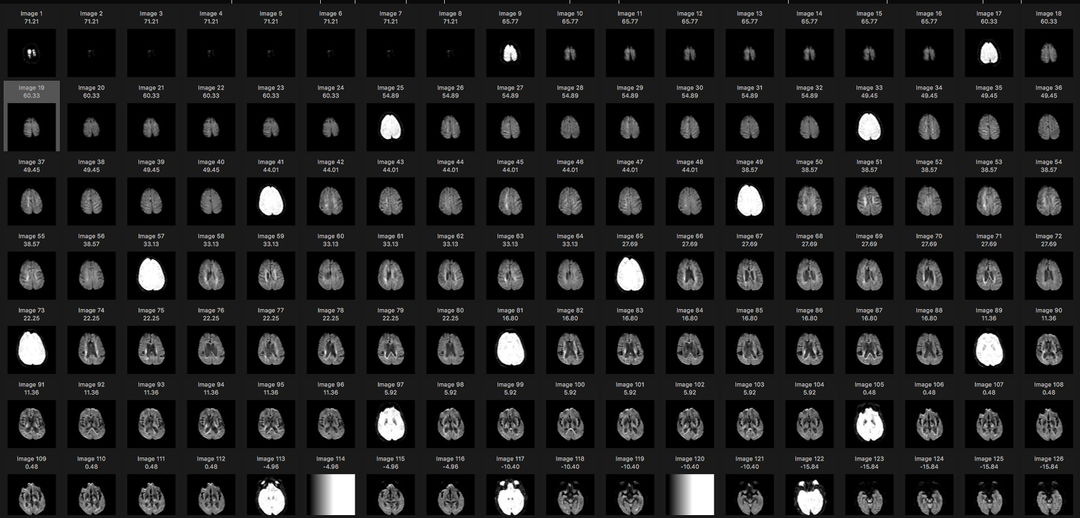

The original data set was flat collection of DICOM files as provided on CD by a hospital. The contents of this folder were imported into the Osirix Lite viewing software. The viewing software organized the file set by patient name (there was only one patient) and into three series of scans. The thumbnail images for one such series is shown:

MRI scan series from DICOM folder generated by Osirix software